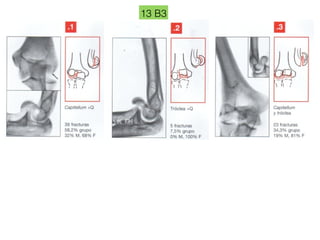

13 B3